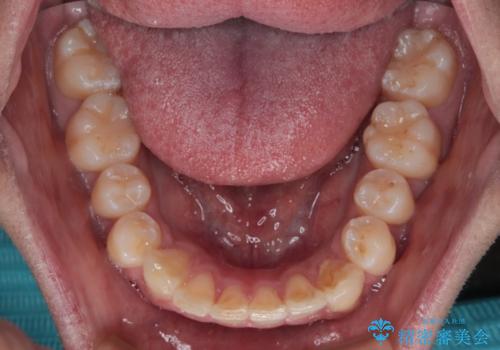

- 前歯のデコボコを治したいとのことで来院された患者様です。

上下顎ともに歯列全体の後方移動とIPR(歯と歯の間を削る)によってデコボコが解消するように設計し、インビザラインにより治療を行うこととしました。

下顎前歯は後戻りを起こしやすいため、舌側を細いワイヤーで固定し、マウスピース型リテーナーで保定を行うこととしました。